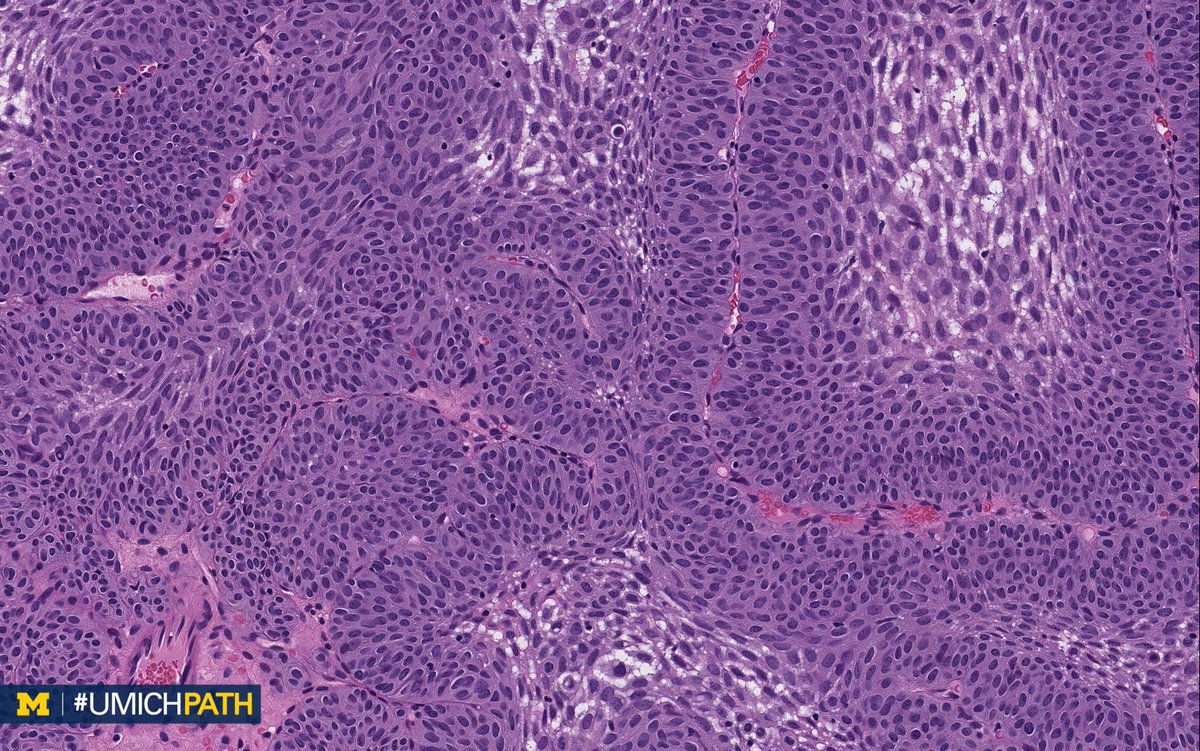

Usually has a surface papillary component. Papilloma of the bladder is a fairly common pathology of the urinary system, but to call exactly the cause that would explain the emergence of formations impossible. Its morbidity accounts for 1.4% to 2.2% of all urothelial neoplasms (9,38).

Inverted papilloma is rare and can occur anywhere in the genitourinary tract but is most common in the bladder.

The biopsy came back as benign. The inverted papillomas of the nose and sinuses are benign, but they can be aggressive and invade the. A neoplasm of the bladder in which the epithelial cells grow downward into the underlying supportive tissue, which often causes hematuria. Inverted papillomas are nasal tumors that originate in the mucosal membrane of the nasal cavity and paranasal sinuses.